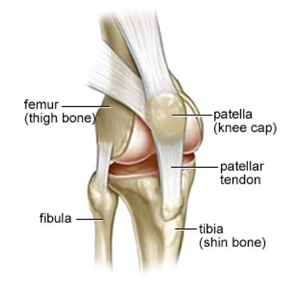

Anything that increases the loading on the knee cap or changes the way it moves over the knee joint can contribute to Patello-Femoral pain. Typically a number of bio-mechanical factors cause the kneecap to be pulled laterally (to the outside). Instead of sliding nicely in its groove on the femur (thigh bone), it rubs against the outside of the groove producing pain and occasionally a grinding sound known as crepitus. The bio-mechanical factors include bony variance, foot over-pronation, weak quads and hip stabilisers, tight quads or ITB.